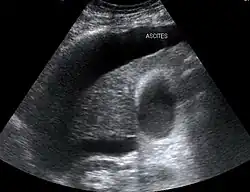

Large volume abdominal ascites

The use of ultrasound has become the standard of care when preparing a patient for paracentesis. Confirmation of an ascitic effusion reduces the risks associated with a dry or blind tap of the abdomen. Anatomic landmarks, such as the midline linea alba approach, were traditionally used as reference points for needle insertion. Phased array or curvilinear ultrasound transducers are typically used in the hospital and outpatient setting to identify ascites in the abdominal cavity. Fluid within the abdominal cavity appears hypoechoic or anechoic (black) on ultrasound. Morison's pouch (hepatorenal recess) is a common starting location in concordance with ultrasound FAST (focused assessment with sonography for trauma) exam. Fluid collection can occur in a number of different locations and may be difficult to find, especially if the patient only exhibits a small volume of ascites. Measurement of the amount of fluid within the abdominal cavity is not necessary or very successful. Identification of sufficient fluid within the abdominal cavity for fluid analysis or to achieve a therapeutic benefit is all that is required to proceed to paracentesis. Ultrasound guidance of the paracentesis can also be used as an additional safety measure to ensure the needle stays within the ascitic fluid and avoidance of important vessels within the abdominal cavity.[5]

Small fluid collection in Morison's pouch